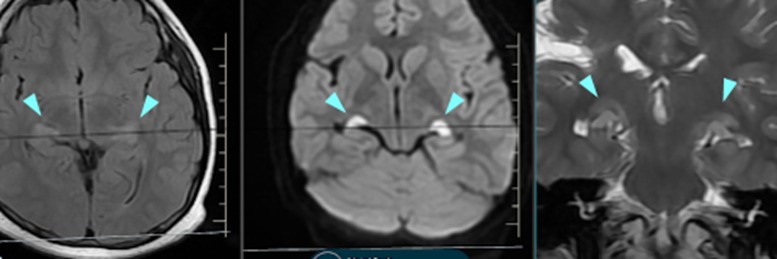

artery of percheron infarcts

Small acute infarcts involving bilateral thalami at paramedian aspect (artery of percheron infarcts). Associated multifocal...